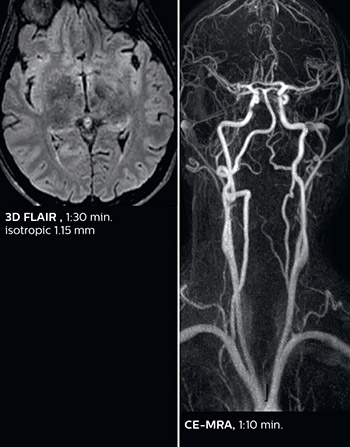

According to Dr. Savatovsky, Ingenia Elition has an impact in virtually all examinations. “We can either make the scanning faster compared to our older Ingenia 3.0T, or we save enough time so that we can add sequences we wouldn’t perform otherwise, or increase resolution. So, I think it has benefits for most of our patients.” “Some routine exams that we use every day have been shortened since we started using Elition. For example, we now use mostly a comprehensive stroke protocol (high b-value diffusion, fast 3D FLAIR, TOF, supra-aortic vessels angiography, SWIp, T1 post gad) that lasts 10 to 11 minutes, but our fast stroke protocol takes only 7 minutes. Our routine IAC needs about 10 minutes scan time and our comprehensive brain MS examination requires no longer than 13 minutes of scan time. Our ability to reduce acquisition times of most sequences helps to shorten total examination times, which in turn helps us to increase the number of patients we scan per day. “The main breakthrough for us was that Compressed SENSE and Multiband SENSE have allowed us to accelerate our examinations. Alternatively, we can invest the time gained in obtaining higher spatial resolution to see more details, or we can add additional sequences,” says Dr. Savatovsky. “That’s a big improvement from what we did before.”

The abbreviated MS protocol for brain is only around 9 minutes, so in case of suspected multiple sclerosis, one or two more advanced sequences may be added, such as PSIR (phase sensitive inversion recovery) or susceptibility-weighted sequences to help us make more confident diagnoses in these inflammatory cases.

In this example, the optional 3D multishot susceptibility weighted sequence with 0.6 mm isotropic voxels is 2 lesions with a central vein sign (arrows) and one lesion with a phase-rim sign (arrowhead). The total scan time, including SmartBrain and axial PD/T2 3mm, is 11:10 min. and is 18:30 min. with the optional 3D PSIR and 3D SWI multishot included.

“We used to have long examination times for certain types of patients, a few lasting more than 40 minutes,” says Dr. Savatovsky. “What is remarkable, is that now all these examinations are below 30 minutes, which opens up opportunity to add more sequences when needed. It’s really hard to keep a patient for more than 40 minutes in the scanner, but because we have now cut scan times by at least 10 minutes, we can add more sequences without making the exam too long. And this is where the new system helps us make a difference. Examples include our examinations for informing brain tumor classification or giant cell arteritis workup, or for intracranial wall imaging – so in patients where we need several advanced sequences or high resolution sequences.” “We added three additional sequences in our brain neoplasm classification exam: a 3D SWI sequence, APT and ASL on top of 3D morphologic sequences, an isotropic DSC (dynamic susceptibility contrast) and multivoxel spectroscopy. I think that in patients that need a classification for brain mass, for example, we can provide a more detailed and confident diagnosis than before, allowing the clinicians to decide for either a medical workup if no tumor is suspected, or for neurosurgery as soon as possible if a neoplasm is suspected.” “In multiple sclerosis patients, we increasingly include a multishot susceptibility sequence [3] in our routine cases, thanks to the shorter scan times. Our abbreviated MS protocol for brain is around 8 to 9 minutes, so we can ask for one or two additional sequences to visualize the central veins, or to get an additional contrast to better depict posterior fossa lesions. In cases of white matter lesions of unknown significance on FLAIR images, for example when we see high signal hyperintensities in the brain, we can add on more advanced sequences such as PSIR (phase sensitive inversion recovery) or susceptibility-weighted sequences to help us in distinguishing between MS and nonspecific or vascular abnormalities in these inflammatory cases.”